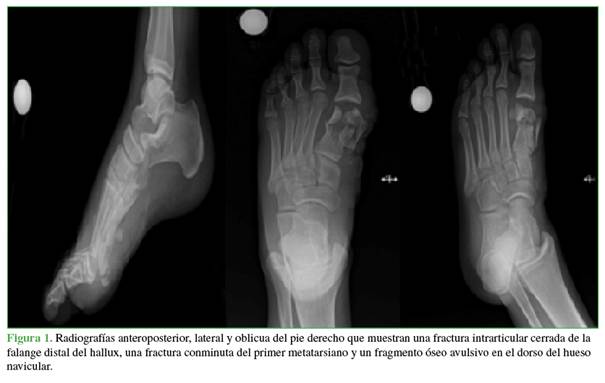

Se solicitaron radiografías para caracterizar el compromiso óseo y se observó una fractura intrarticular cerrada de la falange distal del hallux, una fractura abierta conminuta del primer metatarsiano y un fragmento óseo avulsivo en el dorso del navicular (Figura 1). En consecuencia, fue inmovilizado con una férula suropédica y se continuó el tratamiento antibiótico, según el protocolo institucional, con cefazolina 2 g, por vía intravenosa, cada 8 h, por 72 h. Los médicos del Servicio de Ortopedia programaron el lavado, el desbridamiento y la corrección quirúrgica de las fracturas.